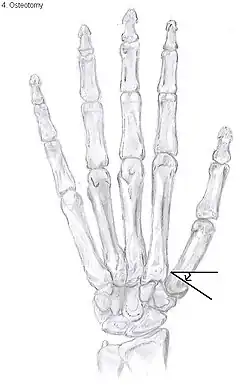

Osteotomy of the thumb

Metacarpal osteotomy

The aim of metacarpal osteotomy is to change the pressure distribution on the TMC joint. The hope is that this will slow the pace of development of osteoarthritis. There is no evidence that this procedure can modify the natural course of TMC OA. Osteotomy may be considered for people with mild arthritis.[24]

During osteotomy, the metacarpal is cut and a wedge shape bone fragment is removed to move the bone away from the hand.[35] Postoperative, the thumb of the patient is immobilized using a thumb-cast.

Possible complications are non-union of the bone, persistent pain related to unrecognized CMC or pantrapezial disease and radial sensory nerve injury.[24]